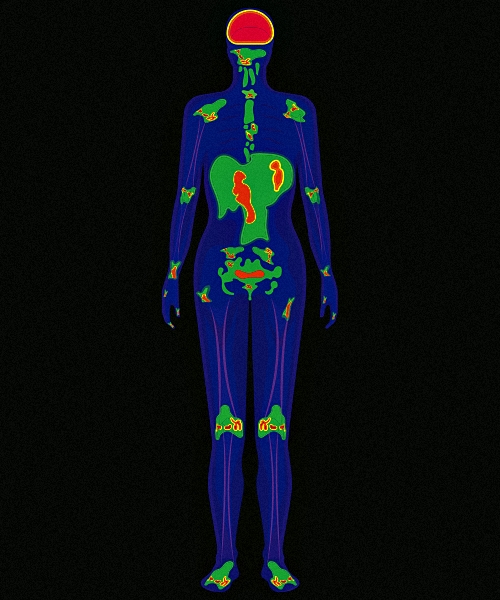

Cintilografia

Presente na medicina nuclear, esse exame utiliza pequenas quantidades de materiais emissores de radiação, eles formarão imagens diagnósticas.

A medicina nuclear é capaz de detectar anormalidades que nenhum outro método consegue, por isso realize seus exames no Ultra-X. Conheça nossos serviços: Miocárdio, Tireoide, Metástase, Renal, Cerebral, Fígado e baço, Glândulas salivares, Vias biliares, Testicular, Óssea, Mama, Pulmonar.